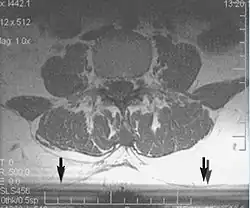

Fig. 11. Slice-to-slice interference (T1 axial study of lumbar vertebrae).[1]

Non-uniform RF energy received by adjacent slices during a multi-slice acquisition is due to cross-excitation of adjacent slices with contrast loss in reconstructed images (Fig. 11). To overcome these interference artifacts, the acquisition of two independent sets of gapped multi-slice images need to be included, and subsequently reordered during display of the full image set.[1]